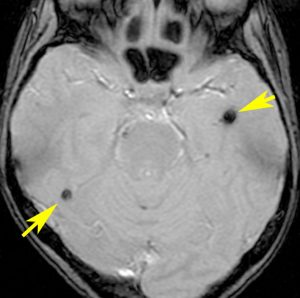

海綿状血管腫 微小血管障害

多発性微小脳出血

- ほとんどが小児に生じるものです

- 放射線治療を受けた患者の40%くらいでみられます

- 照射後10年くらい長期観察をしていると実際に非常に高頻度にみます

- 海綿状血管腫は,放射線誘発2次腫瘍というよりも,放射線による脳内小血管損傷による血管障害として捉えた方がよいです

- T2スターというMRI画像で発見できます

11歳の時に全脳室照射24グレイ・12分割を受けた女の子です。10年以上経過して,脳のあちこちに小さな黒い点状のものが見えるようになってきました。これは子供の頃に放射線治療を受けた人に多く,なんでもないもので症状は出ませんし,ほっておいていいものです。微小な脳静脈の放射線損傷による血液の漏れだと考えられています。

- 低信号(黒いシミみたいなもの)として脳内たくさん見られることがあります

- これは血液の中の鉄分が脳に滲み込んだ形跡をみているものです

- だから,海綿状血管腫とは言わないで,blood leak(血液が漏れた痕跡)と読んだ方がいいものです

- 海綿状血管腫というと腫瘍みたいだからです

- 年月の経過とともに数が増加します

- 海綿状血管腫は発生しても何ら症状を呈することはありません

- 治療をせずに放置します

- まれに小さな脳出血を生じますが,経過を見れば血腫は自然に吸収されます